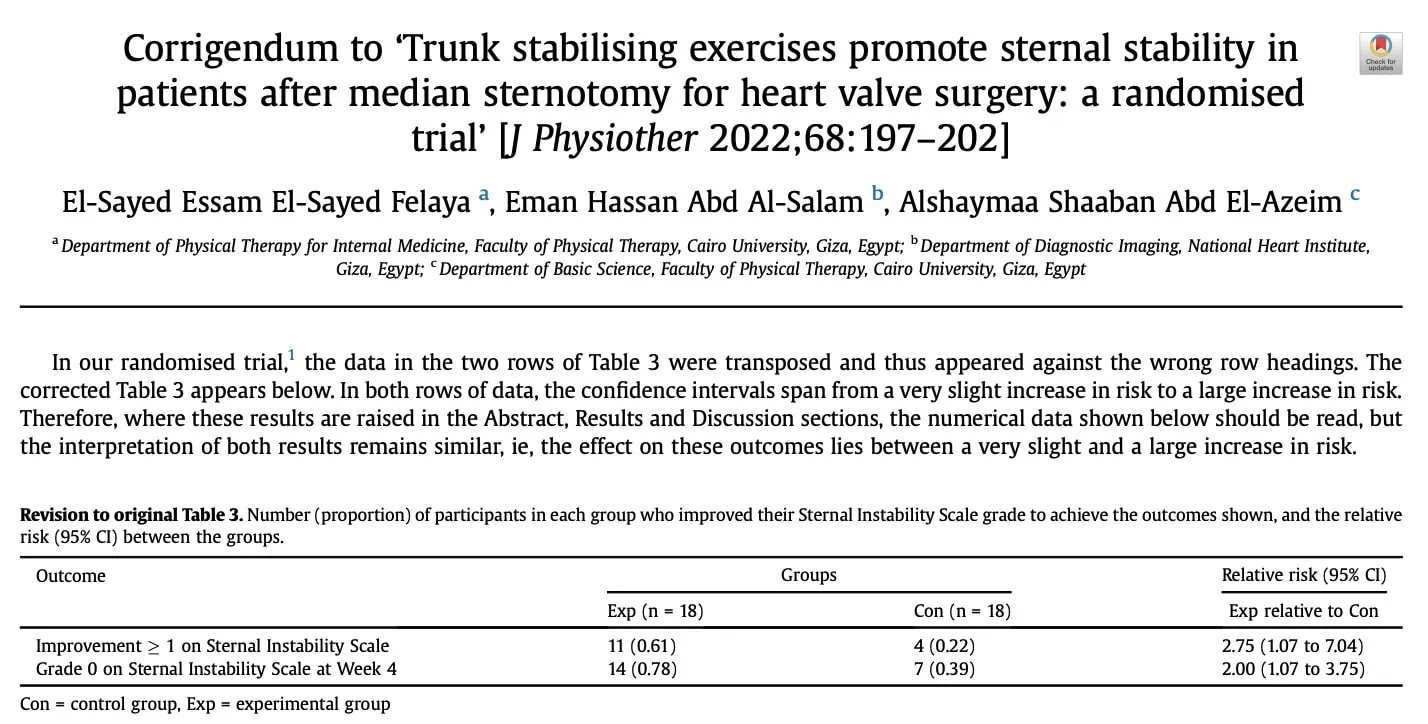

次要结果显示,实验组在胸骨不稳定性量表上至少提高一个等级的可能性是实验组的两倍(RR 2.00,95% CI 1.07 至 3.75)。 实验组在四周内实现胸骨临床稳定(0 级)的几率几乎是实验组的三倍(RR 2.75,95% CI 1.07 至 7.04)。

次要结果支持主要分析,但置信区间更宽。 因此,胸骨不稳定性量表的结果具有更大的不确定性。 一些参与者有了明显改善,而另一些则改善甚微。 不过,胸骨不稳定性量表是一种主观测量方法,因为它是在体格检查时评估胸骨的移动程度。 然而,这需要专业知识,而且要评估的运动量非常小,极易出现误差和研究人员的偏差。 这也许可以部分解释为什么这些研究结果的置信区间要大得多。 El-Ansary 等人(2000 年)报告称,经过培训和标准化检查程序后,评分者之间(99%)和评分者内部(98%)的可靠性达到了完美水平。 不过,这项研究的主观性以及对这种细微动作的触诊可能需要进一步验证。